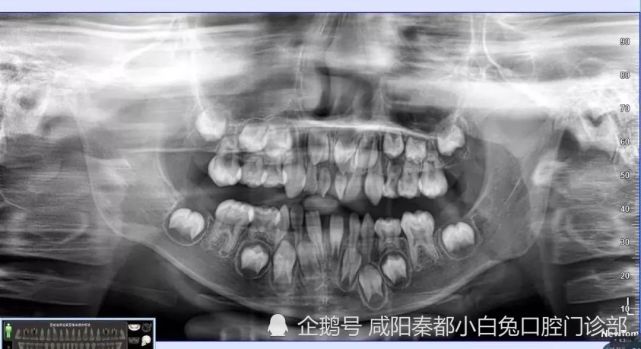

乳牙x光

乳牙x光,

5-2颗乳牙那么大.

出生时,颌骨中已包含乳牙胚与恒牙胚两副发育成熟的牙胚.